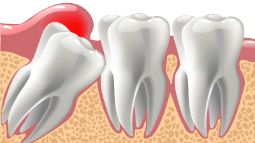

Удаление ретинированного/дистопированного зуба

Зубы мудрости начинают расти, когда остальная челюсть уже сформировалась, поэтому неправильный рост и деформированная коронка представляют собой распространенную проблему среди пациентов стоматологических клиник.